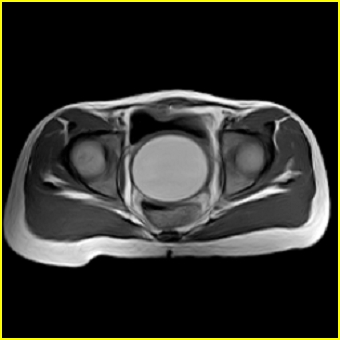

女、15岁、下腹疼痛2天,排尿困难1天。查体:处女膜闭锁,距处女膜约4至5cm处扪及一约5cm直径的圆形包块,张力较高,触痛明显、欠活动。b超提示子宫增大伴宫内增强回声团。

影像意见:子宫直肠陷凹积血。

更正影像意见:阴道积血。

处女膜闭锁,阴道积血

处女膜闭锁,阴道积血,子宫积血.

先天性处女膜闭锁,伴阴道积血,不除外先天性阴道粘液囊肿形成。

阴道积血,子宫积血.

子宫及阴道积血。

处女膜闭锁,伴子宫及阴道积血.